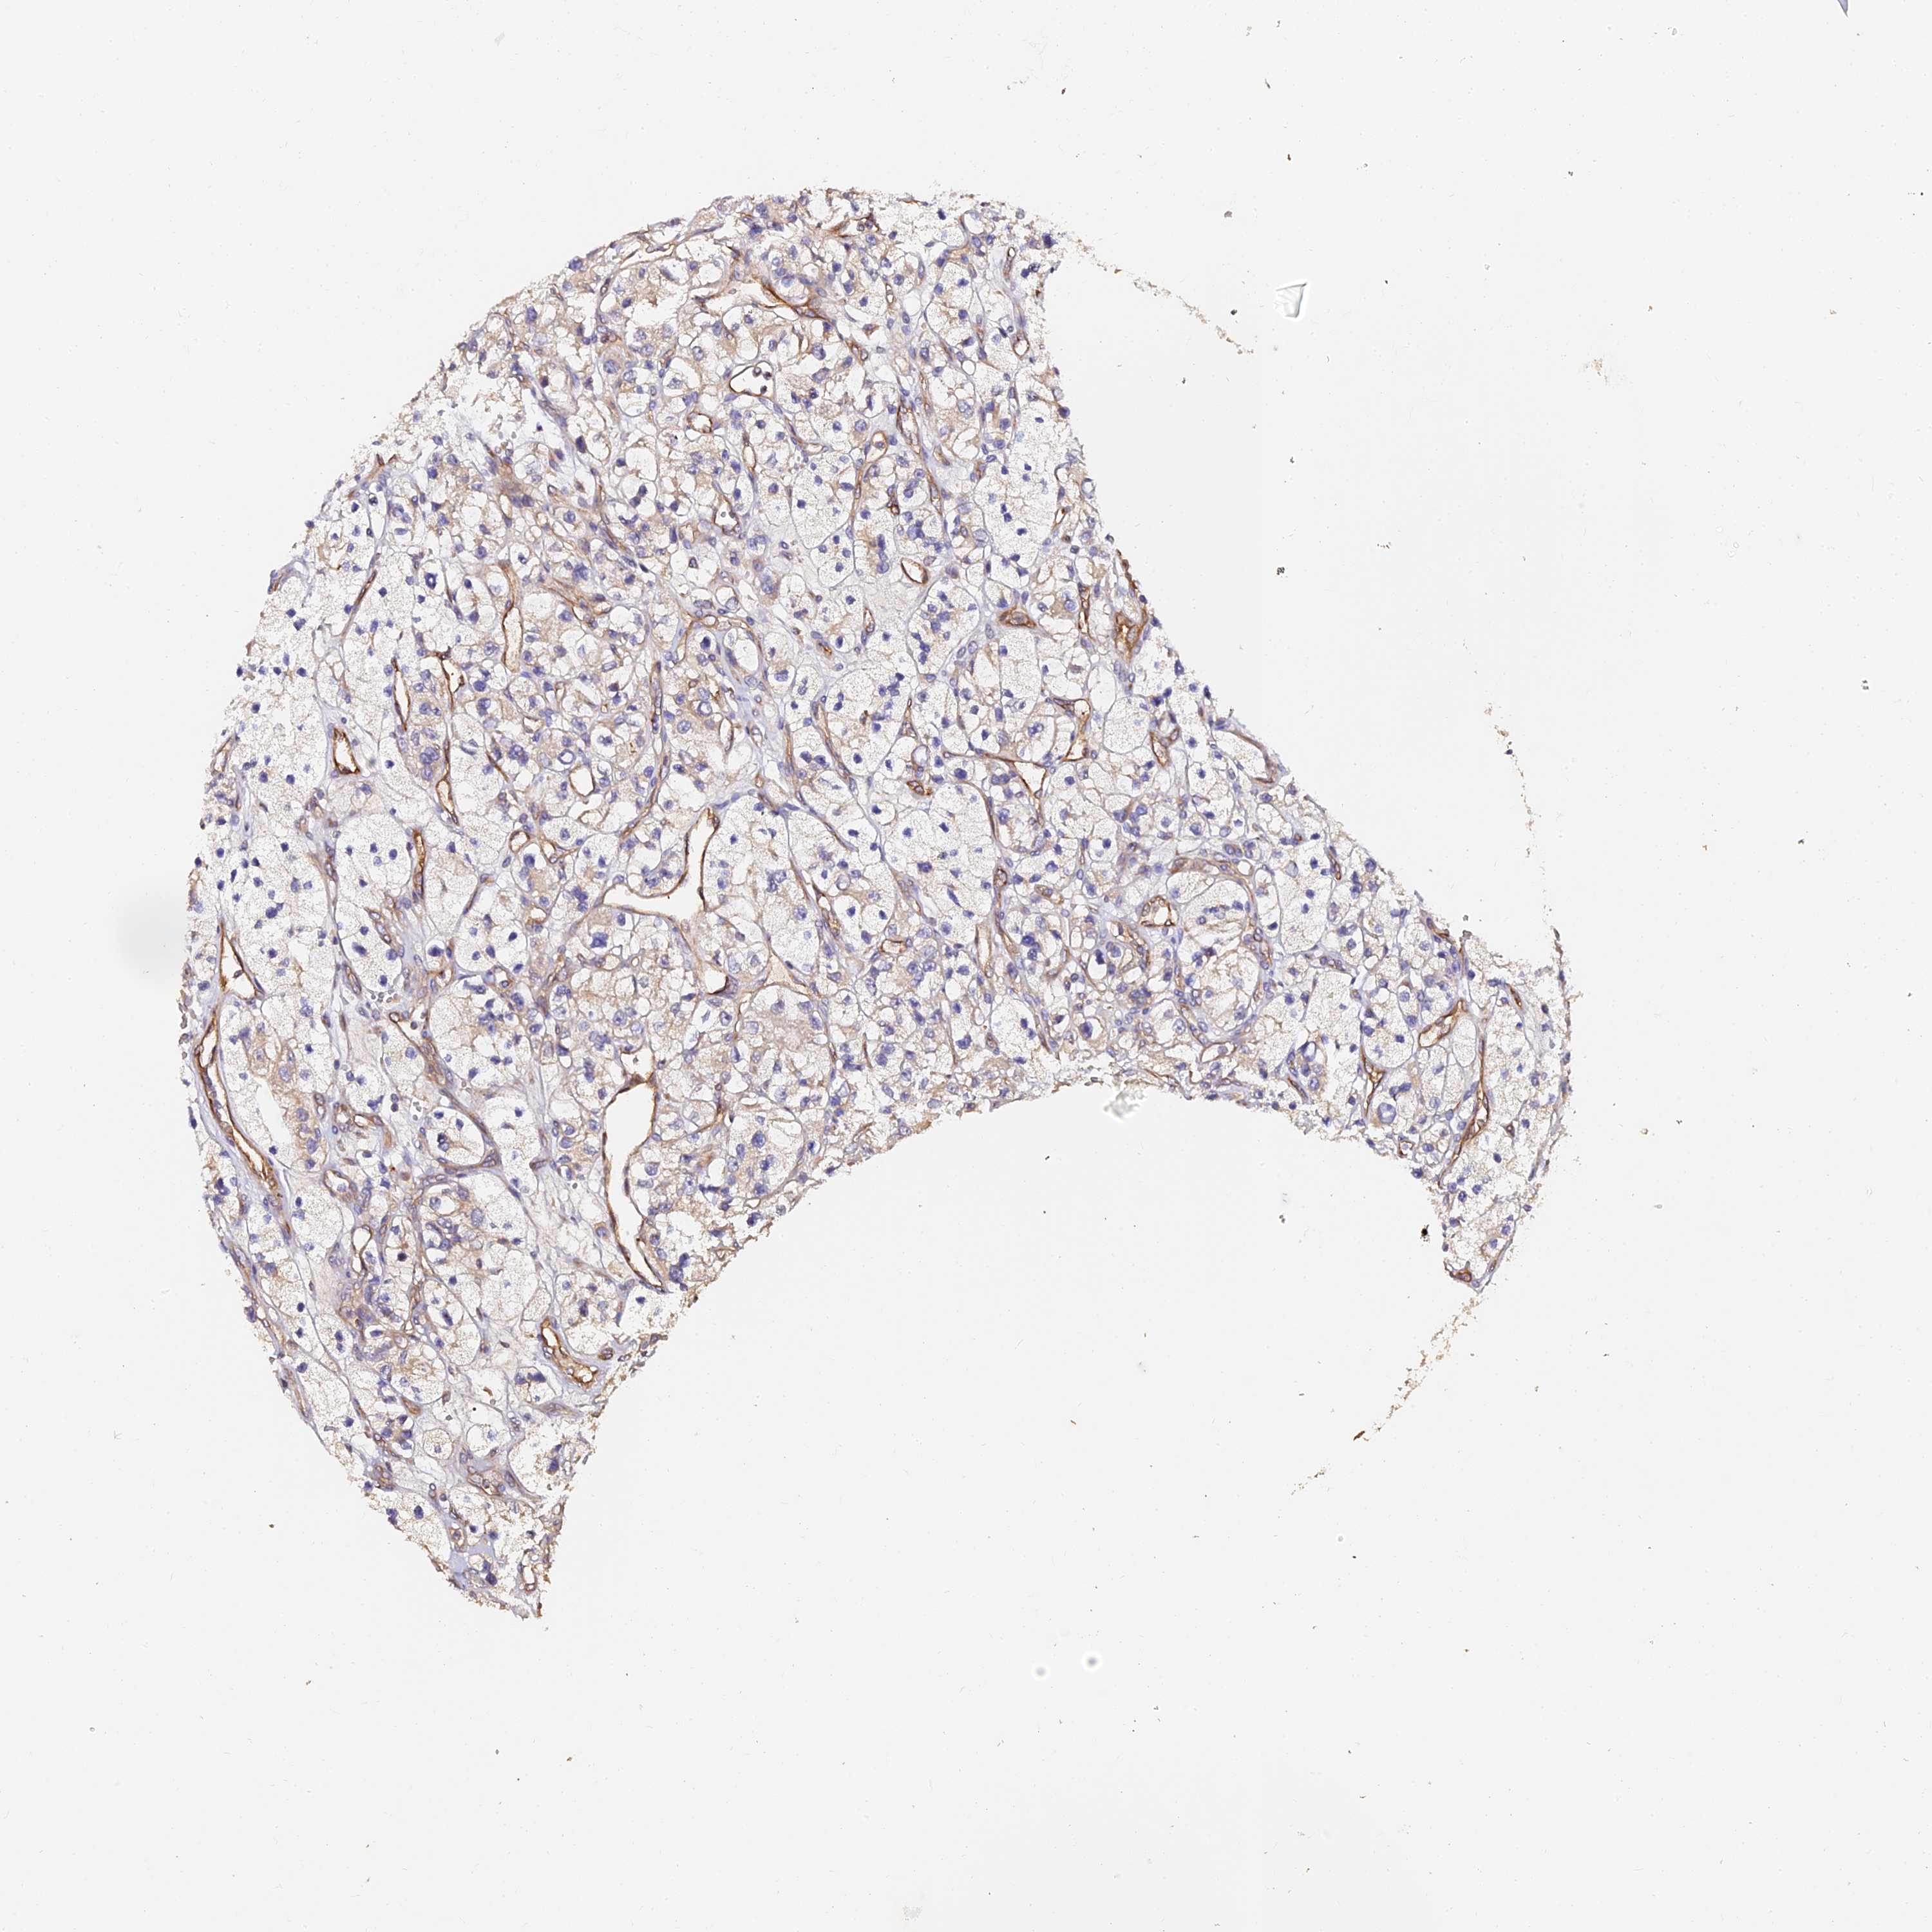

KIDNEY RENAL CLEAR CELL CARCINOMA (VALIDATION) - Interactive survival scatter ploti

The Survival Scatter plot shows the clinical status (i.e. dead or alive) for all individuals in the patient cohort, based on the same data that underlies the corresponding Kaplan-Meier plots. Patients that are alive at last time for follow-up are shown in blue and patients who have died during the study are shown in red.

The x-axis shows the expression levels (FPKM) of the investigated gene in the tumor tissue at the time of diagnosis. The y-axis shows the follow-up time after diagnosis (years). Both axes are complimented with kernel density curves demonstrating the data density over the axes. The top density plot shows the expression levels (FPKM) distribution among dead (red) and alive patients (blue). The right density plot shows the data density of the survived years of dead patients with high and low expression levels respectively, stratified using the cutoff indicated by the vertical dashed line through the Survival Scatter plot. This cutoff is automatically defined based on the FPKM cutoff that minimizes the p-score. The cutoff can be changed by dragging the vertical line or by entering a cutoff value in the square labeled "Current cut-off".

Under the Survival Scatter plot the p-score landscape (black curve; left axis) is shown together with dead median separation (red curve; right axis). Dead median separation is the difference in median mRNA expression between patients who have died with high and low expression, respectively. It is calculated as follows: median FPKM expression of dead patients with high expression - median FPKM expression of dead patients with low expression. This is intended to aid the user in visually exploring custom cutoffs and the associated p-scores and dead median separation.

Individual patient data is displayed and can be filtered by clicking on one or more of the category buttons on the top of the page. Categories describing expression level and patient information include: high, low, alive, dead, female, male and tumor stages. The scale of the x-axis can be toggled between linear and log-scale by clicking on the "x log" button. Mouse-over function shows TCGA ID, patient information and mRNA expression (FPKM) for each patient.

& Survival analysisi

Kaplan-Meier plots summarize results from analysis of correlation between mRNA expression level and patient survival. Patients were divided based on level of expression into one of the two groups "low" (under cut off) or "high" (over cut off). X-axis shows time for survival (years) and y-axis shows the probability of survival, where 1.0 corresponds to 100 percent.

TDO2 is not prognostic in Kidney Renal Clear Cell Carcinoma (validation)

Best expression cut offi

Based on the FPKM value of each gene, patients were classified into two groups and association between prognosis (survival) and gene expression (FPKM) was examined. The best expression cut-off refers the FPKM value that yields maximal difference with regard to survival between the two groups at the lowest log-rank P-value. Best expression cut-off was selected based on survival analysis .

When clicking on this number, the vertical dashed line indicating cut-off, the interactive survival plot, and the Kaplan-Meier curve will be adjusted to show results based on the best expression cut-off.

: 0.39

P scorei

Log-rank P value for Kaplan-Meier plot showing results from analysis of correlation between mRNA expression level and patient survival.

N/A

TCGA RNA samplesi

RNA-seq data is reported as average FPKM (number Fragments Per Kilobase of exon per Million reads), generated by the The Cancer Genome Atlas (TCGA) .

Normal distribution across the dataset is visualized with box plots, shown as median and 25th and 75th percentiles. Points are displayed as outliers if they are above or below 1.5 times the interquartile range. FPKM values of the individual samples are presented next to the box plot.

Average pTPM 1.4

Number of samples 100